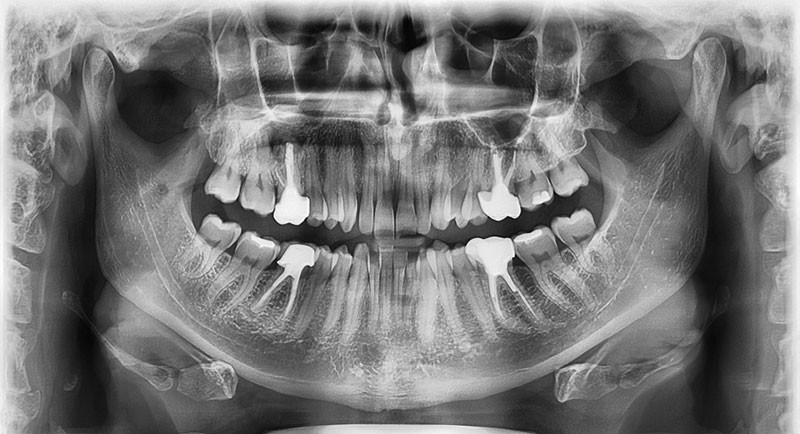

Le cas exposé dans les figures 1 à 8 présente un défaut osseux en dedans des couloirs alvéolaires.